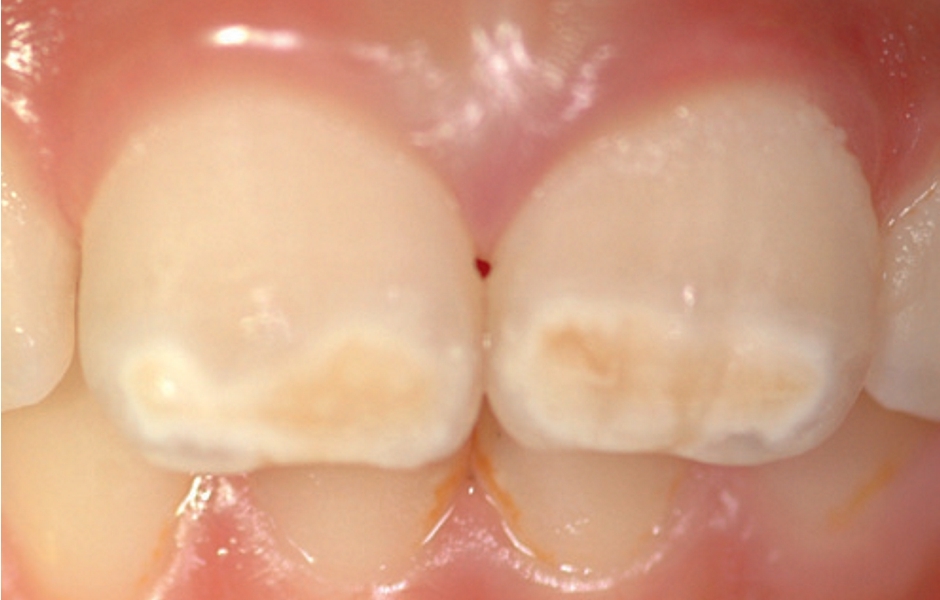

Klinický vzhled

• Ohraničené opacity v rozpětí od krémově bílé, přes žlutou až po hnědé diskolorace • Poškozená sklovina má normální tloušťku (dokud nedojde k posterupčnímu odlomení skloviny) • Léze se mohou vyskytovat asymetricky • Je-li závažně poškozen první molár, existuje zvýšená pravděpodobnost, že protilehlý molár bude rovněž poškozen • Léze na centrálních řezácích jsou obvykle mírnější, někdy však mohou být neestetické

Mírná MIH